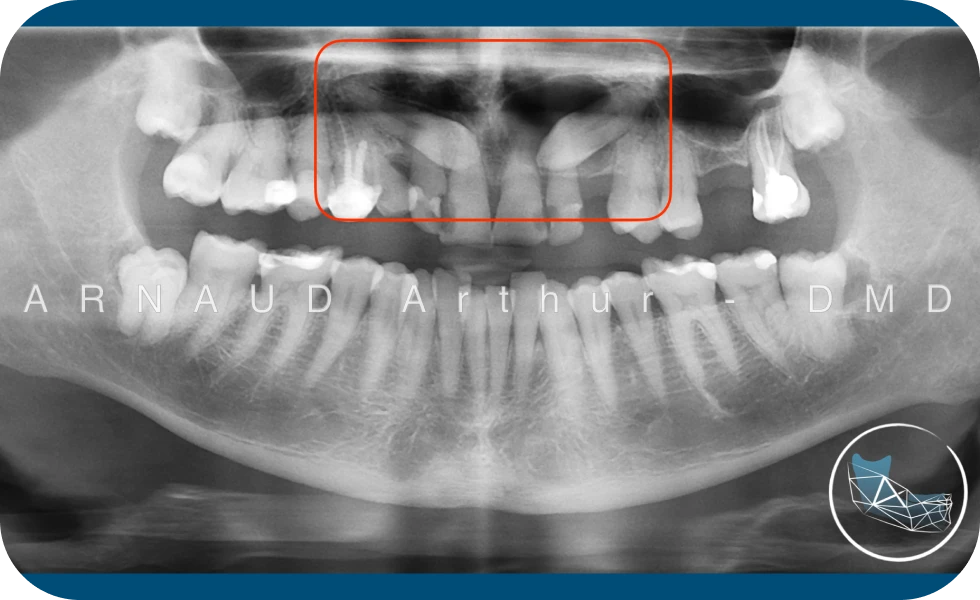

Cas de lésions sur les canines incluses chez un patient adulte